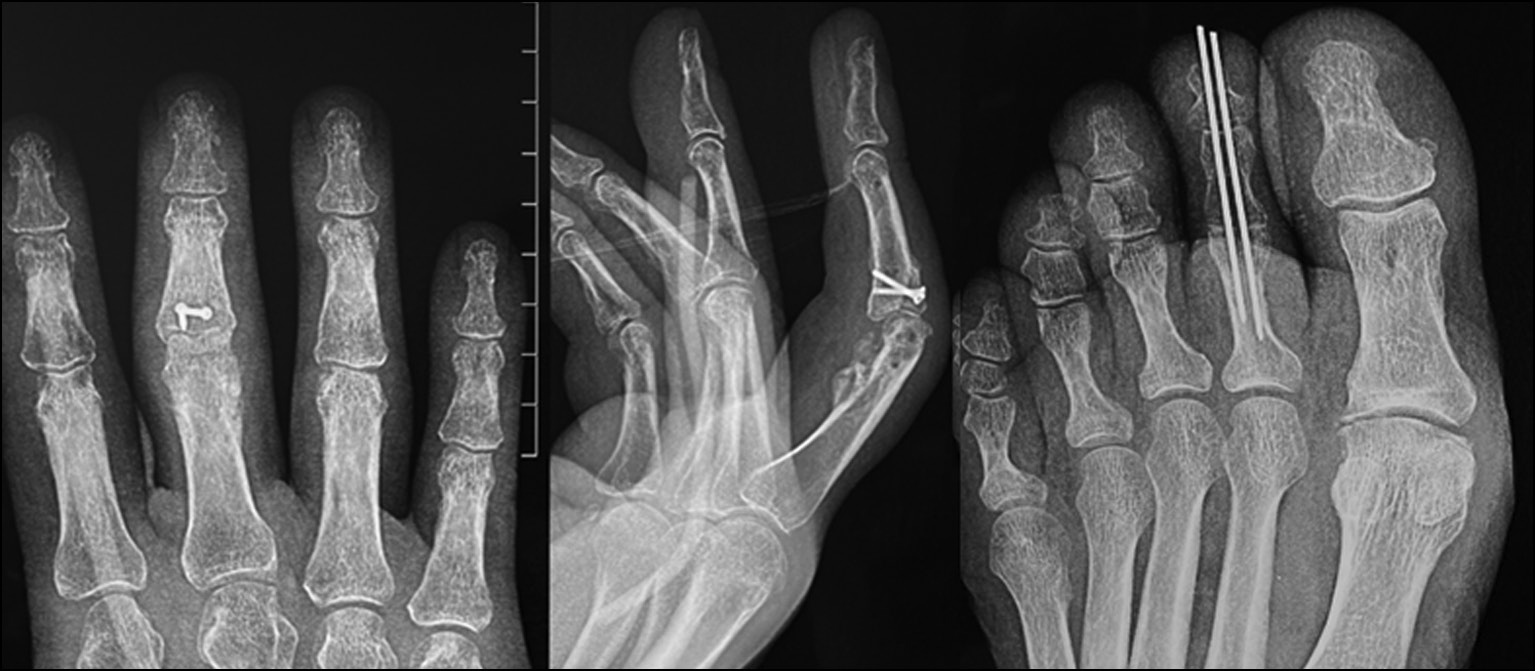

Fig. 24. Appearance before surgery.

Fig. 25. X-ray picture before surgery.

Fig. 26. X-ray control after surgery. Suzuki pins and rubber traction system.

Fig. 27. Appearance after surgery. Suzuki pins and rubber traction system.

Fig. 21. X-ray control after osteosynthesis of the graft and arthrodesis of the proximal interphalangeal joint of the toe.

Fig. 22. X-ray control 2 months after the operation.